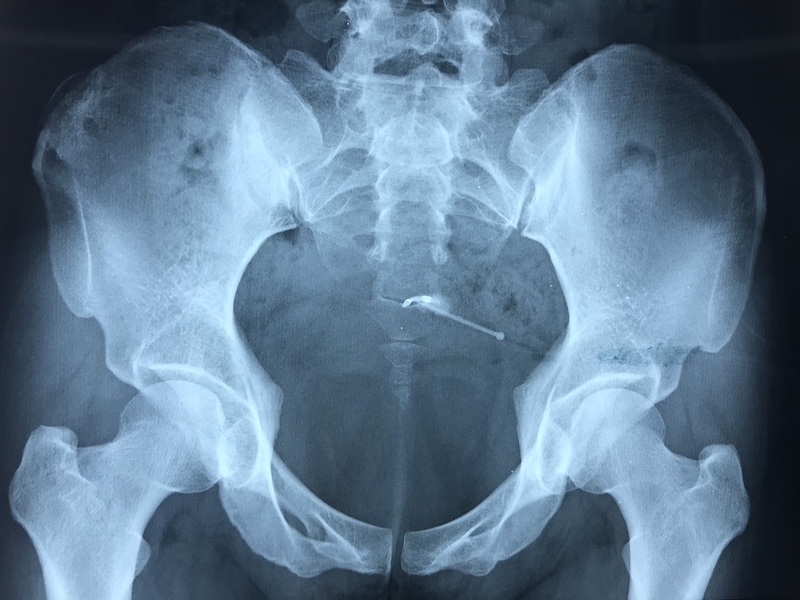

Với những trường hợp này, vòng tránh thai vô tình trở thành dị vật trong tử cung. Để vòng tránh thai quá hạn trong cơ thể không chỉ làm tăng nguy cơ mắc bệnh lý phụ khoa mà còn trong cơ thể có thể bị lệch, nứt, gãy, thậm chí xuyên qua ổ bụng và bám vào các cơ quan xung quanh gây ra tổn thương, viêm nhiễm, thậm chí thủng tử cung, thủng ruột, xuất huyết, nhiễm trùng huyết,...

Phẫu thuật lấy vòng tránh thai chính là biện pháp điều trị tối ưu trong những trường hợp vòng tránh thai “đi lạc” này. Phẫu thuật lấy vòng tránh thai là phương pháp được chỉ định nhằm đưa vòng tránh thai ra khỏi cơ thể người phụ nữ. Phẫu thuật này thường được thực hiện bằng kỹ thuật nội soi ít xâm lấn để giảm tối đa biến chứng cho người bệnh. Phương pháp nội soi mang lại nhiều ưu điểm như hạn chế xâm lấn, ít đau, nhờ đó người bệnh cũng nhanh chóng hồi phục và ít để lại sẹo.